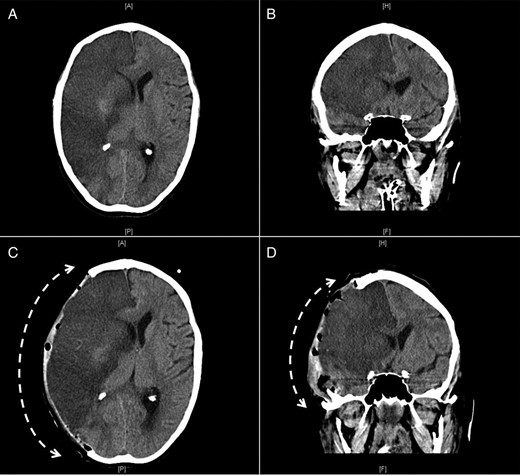

Repeated CT scan of the head 24 h later confirmed the diagnosis of an evolving large right hemisphere infarction involving both anterior and middle cerebral arteries territory with midline shift (Fig. 3A and B). Hemicranial decompression was performed and a follow-up CT scan of the head, 24 h later, showed transcranial herniation of the right cerebral hemisphere with reduction of the midline shift (Fig. 3C and D). Likewise, because of the multiplicity of the emboli, she also developed occlusion of the aorta as well as in both femoral systems and right popliteal artery that required corresponding embolectomies and bilateral aortofemoral bypass surgery. The pathological examination of the emboli confirmed the diagnosis of atrial myxoma.

Axial (A and C) and coronal (B and D) CT images of the brain showing a large infarct in the area of the right middle cerebral artery before (A and B) and after (C and D) right hemicranial decompression with transcranial herniation of the right cerebral hemisphere (interrupted curved arrows).